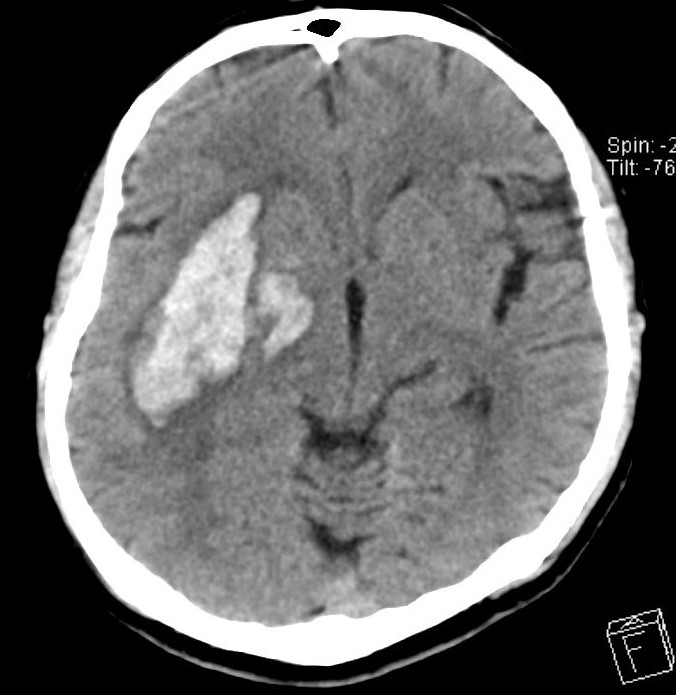

脳内出血とは『脳の中に出血する病気』です。脳の中には細い血管が走っています。この血管が破裂すると脳内出血になります。脳内出血を起こすと脳の中に血液の固まり(血腫といいます)ができ、その周囲の脳組織は破壊されてしまいます。出血した場所に応じてさまざまな症状が出ますが、どこの場所であっても大きな出血では意識が悪くなり、生命に関わる状態になります。

図:脳内出血のCT